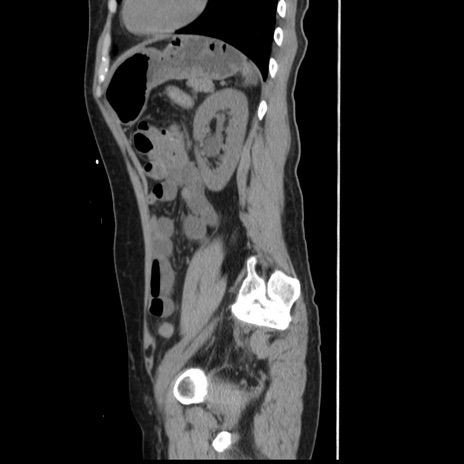

横断像

【症例】 50歳代女性

【主訴】 腹痛

【現病歴】前日生レバーを食べた。今朝に排便あり。 昼前に突然発症の腹痛を生じ、当院救急外来を受診した。

【既往歴】 子宮筋腫にてで子宮全摘後

【身体所見】 意識清明、腹部:平坦、軟、下腹部やや左を中心に圧痛・反跳痛あり、筋性防御あり

【データ】WBC 7800、CRP 0.07